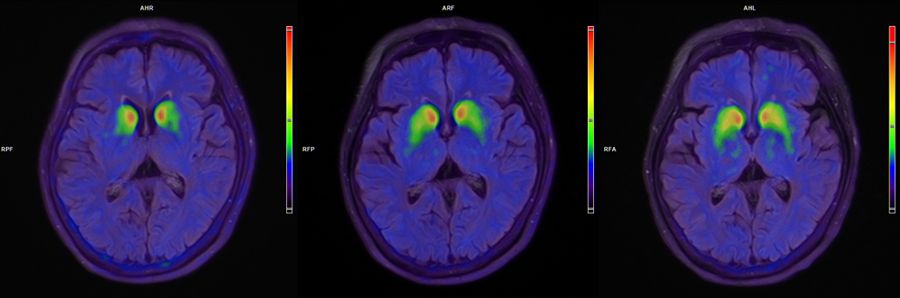

正在进行的临床试验,已显示出国产细胞药物令人期待的前景。2025国际帕金森和运动障碍协会年会上,跃赛生物研发的全球首款“中美双批”自体细胞治疗产品UX-DA001以“最新突破性研究”入选了大会口头报告。上海交大医学院附属瑞金医院在年会上发布了首例帕金森病患者治疗后6个月的随访数据:患者运动功能显著改善,MDS-UPDRS-Ⅲ评分在“关期”改善21分,在“开期”改善9分,改善比例均超过45%;每天“关期”时间平均减少3.6小时,无烦人异动症的“开期”时间增加3.3小时;医学影像显示,双侧壳核移植区的多巴胺转运体信号持续增强。

患者脑部术前、3个月、6个月的18F-FP-CIT PET图像